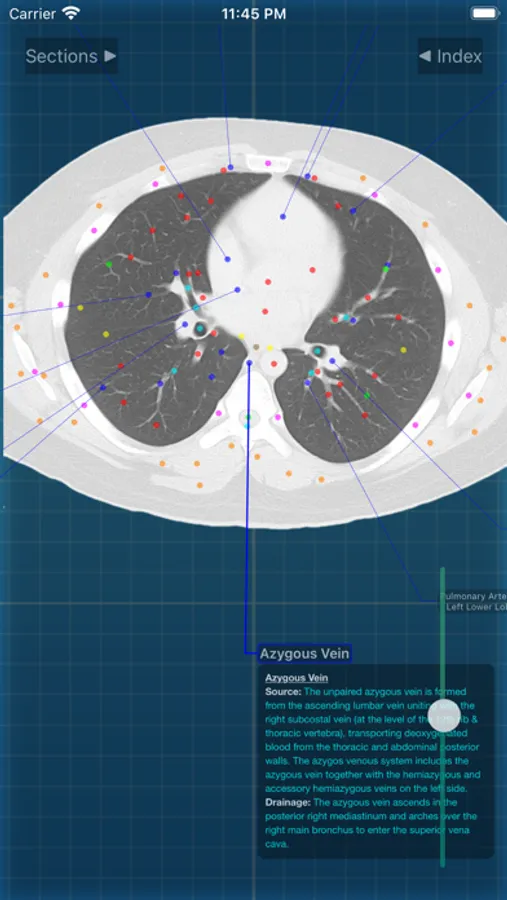

X-Anatomy is a transaxial cross-sectional human anatomy interactive medical imaging atlas using CT images, designed for medical professionals & all students of anatomy.

* Includes hundreds of images from actual human patient body scans.

* Detailed anatomic notes about muscles, vessels, and key anatomic structures

* Complete color-coded index of anatomic structures

* FOLLOW the positions and pathways of your selected anatomic structures automatically as you SCROLL through the image slices.

INCLUDED body section modules cover the major body sections from head to pelvis: CT Brain, CT Neck, CT Sinuses, CT Chest, CT Lungs, CT Abdomen & Male Pelvis, CT Abdomen & Female Pelvis.